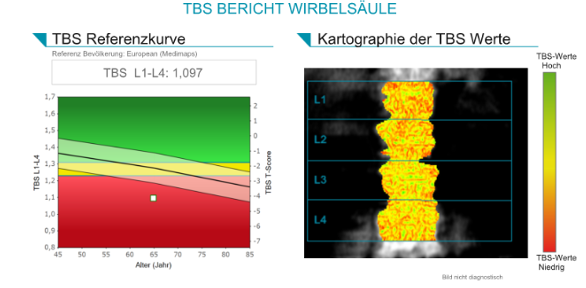

DXA + TBS:

Bei der Patientin liegt einerseits eine hochgradig reduzierte Knochenmineraldichte vor im Sinne einer sekundären manifesten Osteoporose mit multiplen atraumatischen Wirbelkörperfrakturen und andererseits zusätzlich eine

Ursächlich für die ausgeprägte Osteomalazie bei dieser Patientin ist ein schwerer Mangel an Vitamin D3 und Calcium. Ein Marker der Osteomalazie ist die Erhöhung der Alkalischen Phosphatase. Somit steht eine ausreichende Substitution